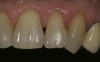

A 55-year-old woman presented with root decay along the left lateral incisor (tooth No. 10) and canine (tooth No. 11) (Figure 1). It was proposed that invisible Class V restorations be placed using an MMID procedure. There are several keys to attaining a successful invisible Class V restoration. Proper understanding of composite resin shade selection, preparation design, and sequence of composite resin layering are important to achieve an ideal blending of the composite resin to the existing tooth. Correct finishing and polishing technique is equally essential in obtaining a seamless esthetic restoration.3,11

Shade selection is always completed before initiating treatment; this is important to develop the proper shade-layering sequence. Composite shades were placed directly on the tooth and shades that matched the areas of the tooth being restored were chosen (Figure 2). To achieve an invisible Class V restoration, a more complex layering process is needed to blend the composite resin.